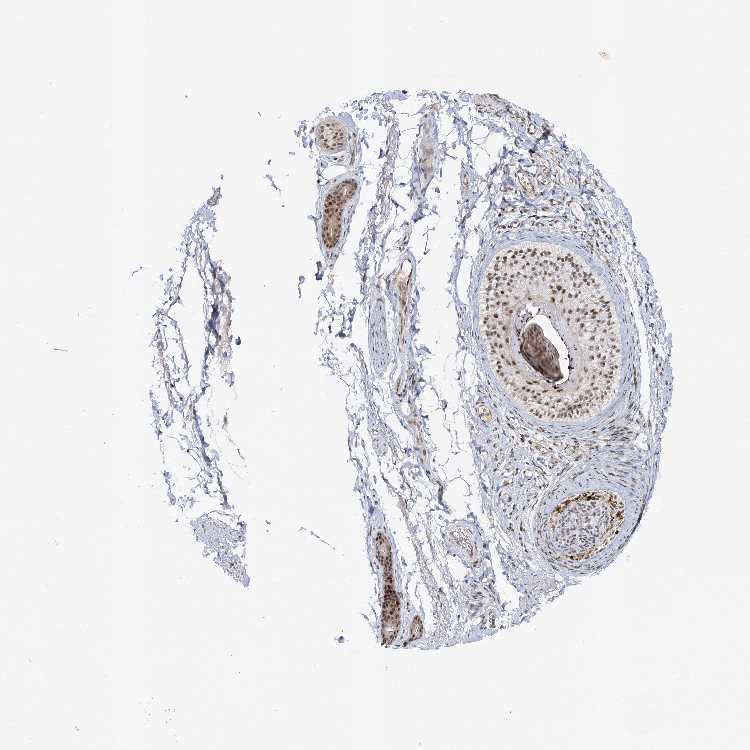

SKIN 1 - Antibody stainingi

Antibody staining in the annotated cell types in the current human tissue is reported as not detected, low, medium, or high, based on conventional immunohistochemistry profiling in selected tissues. This score is based on the combination of the staining intensity and fraction of stained cells.

Each image is clickable and will lead to virtual microscopy that enables deeper exploration of all samples and also displays staining intensity scores, fraction scores and subcellular localization as well as patient and tissue information for each sample.

Antibody HPA038340Antibody HPA038341

Langerhans MediumHigh

Fibroblasts LowHigh

Keratinocytes MediumMedium

Melanocytes MediumHigh

SKIN 2 - Antibody stainingi

Epidermal cells MediumMedium